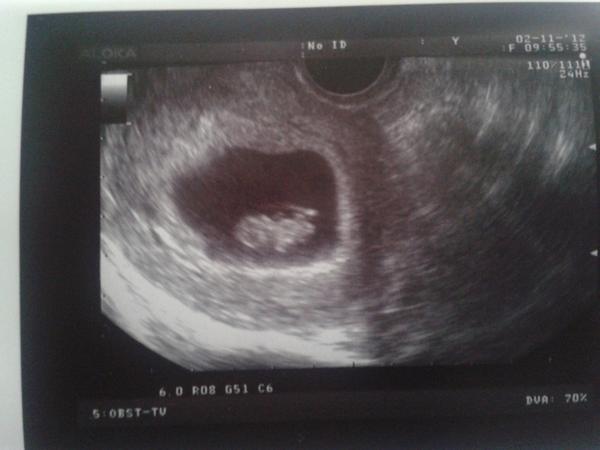

@misa.patrik krásná fotečka prcek už jde krásně vidět.Tak ti držím palečky ať už problémy přestaly,hlavně klideček jo?

@britka děkuji kupodivu jsem strašně vklidu což je vlastně dobře 🙂

@misa.patrik Super gratuluju k miminkovi.Hlavně at už je vše jak má a mužeš si užívat těhulkování naplno 😉

@misa.patrik tak koukám, že vše je v pořádku a hlavně když jsi klidná, tak to půjde všechno hladce až do porodu 🙂 Moc ti to přeju!